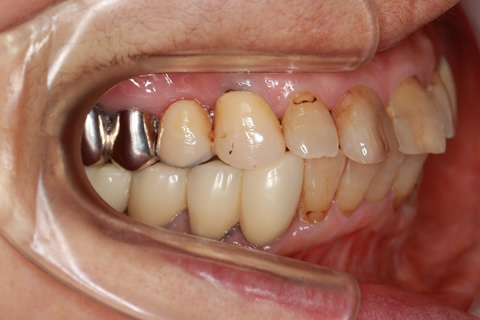

• 症例2

治療前

インプラント埋入時

治療後

年齢・性別

57歳男性

治療期間

3ヶ月

抜歯

なし

治療費

154万円

備考

左上5.6.7 及び左下6.7欠損

治療内容

左上5.6.7と左下6.7欠損部にインプラント埋入

施術の副作用(リスク)

オペによる知覚障害。インプラントによる歯肉炎。インプラント脱落。